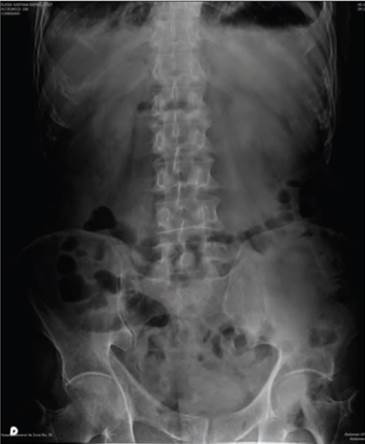

Paciente masculino de 70 años de edad, originario y residente del Distrito Federal, sin antecedentes quirúrgicos ni crónicos degenerativos. Acude al servicio de urgencias por presencia de dolor abdominal en epigastrio e hipocondrio derecho 8/10 en la escala visual análoga, acompañado de náusea, vómito, ausencia de evacuaciones en los últimos 2 días, canalizando gases adecuadamente. A su ingreso al servicio de urgencias, se coloca sonda nasogástrica con gasto de 200 mililitros de líquido gastrobiliar. A la exploración física se encuentran mucosas orales secas, dolor en cuadrante inferior derecho (CID), peristalsis aumentada a este nivel, sin datos de irritación peritoneal. En radiografía de abdomen con presencia de un nivel hidroaéreo a nivel de la fosa ilíaca derecha (FID) (figura 1).

Figura 1 Radiografía de abdomen con adecuada distribuciónaérea a nivel de intestino delgado, presencia de pequeños niveles hidroaéreos a nivel de fosa ilíaca derecha (flecha).